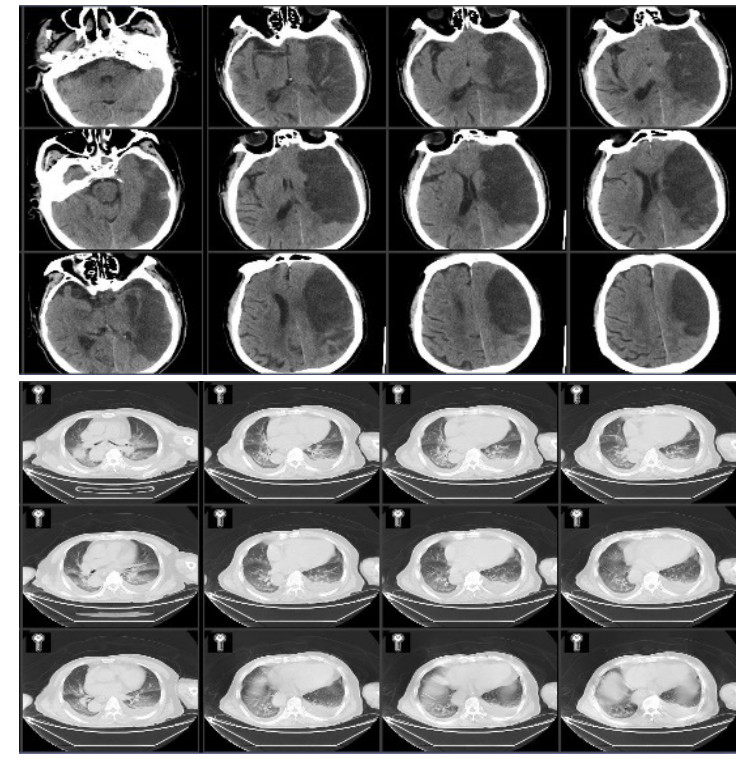

1 资料与方法病例1,男性,87岁,因“洗澡后突发头痛,呕吐半天”急诊入院。既往史有高血压病史数十年,血压控制良好;冠心病史,2007年接受“冠脉搭桥术”,长期服用拜阿司匹林325 mg 1次/d,辛伐他汀80 mg 1次/晚。入院查体:格拉斯哥昏迷评分法(Glasgow Coma Scale,GCS)14分,双瞳等大等圆,光敏,四肢肌力正常,双侧病理征阴性。入院头颅CT(图 1)示小脑蚓部血肿,量约7 mL,四脑室和环池清晰;双侧额顶叶,脑室旁多发缺血腔隙灶,脑萎缩。CTA提示未见明显异常。

| 图 1 2007年5月11日患者入院第1天头颅CT |